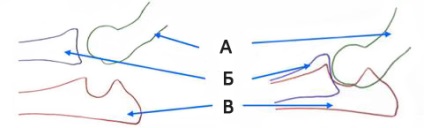

A könyök van kialakítva három csont: a felkarcsont, singcsont és sugarát. Abban az esetben, ha megsértették a csontok azok illeszkedjenek egymáshoz megfelelően. A kapott mismatch ízületi felszínek okoz helyi túlterhelés bizonyos részeinek a könyök: hooklike koronális és folyamatokat, melyek aztán töredezett vagy sérült.

A - felkarcsont

B - sugár

B - ulna